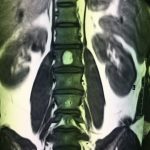

- α

- β

- γ

- δ

- ε

- στ

Εικόνα 2 α,β: Μαγνητική τομογραφία της Ο,Μ,Σ,Σ, (200) Μετωπιαία λήψη (coronal) γ,δ, οβελιαία λήψη (saggital) ε,στ, εγκάρσια λήψη (axial) ακολουθίες Τ1 και Τ2 . Οι λήψεις αυτές αναδεικνύουν την ύπαρξη ευμεγέθους αιμαγγειώματος εντός του σώματος του 1ου οσφυϊκού σπονδύλου.